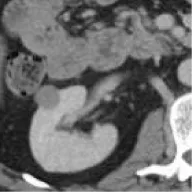

Patients with a pathological diagnosis obtained by biopsy or surgical resection were included in this study. In addition, 80 patients with available arterial/cortical/nephrogenic phase CT image sequences were reviewed (42 with PRCC and 38 with ChRCC). After randomly selecting 6 cases (3 PRCCs and 3 ChRCCs) for testing sets, the images of 74 tumors (39 PRCCs and 35 ChRCCs) were used to build the datasets. The CT images were obtained using various radiology scanners and non-standard protocols. Arterial phase sequences were preferred when multiple phases existed. Whole sequences were retrieved and exported utilizing the hospital radiological database. The window settings were 40 HU (width) and 400 HU (level). Based on the clinical and pathological data, ROIs of sequences were segmented, labeled, and exported with ITK-SNAP by two abdominal radiologists who have experience of more than 10 years in the diagnosis of urinary system tumor. After cross-validation, images that were exported in.jpg size included 857 images of ChRCCs and 997 images of PRCCs. Labeling was applied in the non-graphical layer so that each slice filename contained the case number, gender, age, and histological subtypes. After resizing, images comprised matrices with 256 * 256 pixels in the axial planes. The dataset was divided into the training set and validation set (90% for the training set and 10% for the validation set).